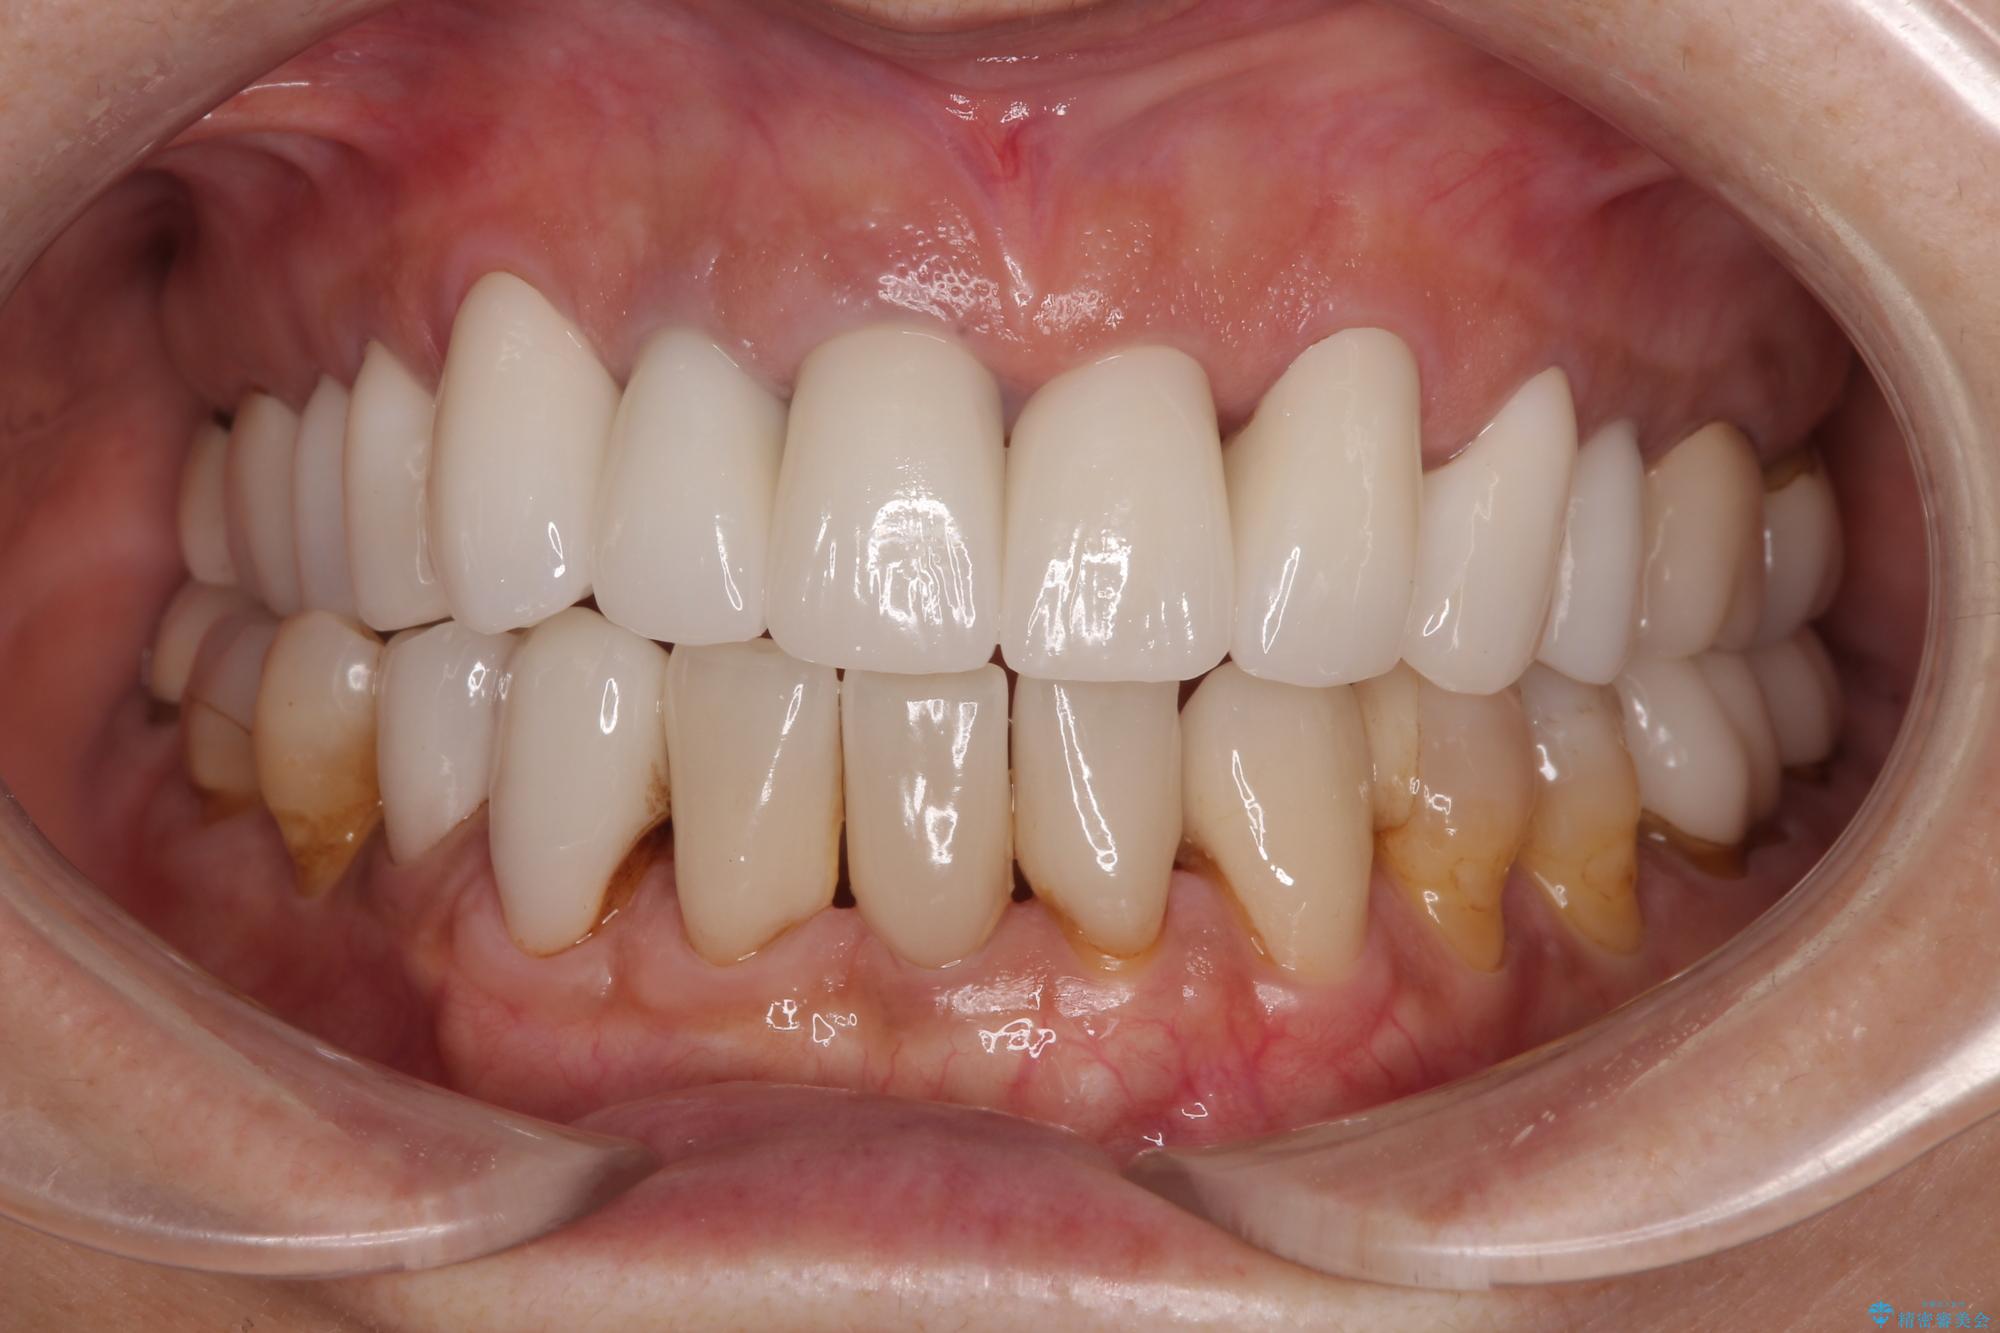

不釣り合いで境目の露出した前歯 オールセラミッククラウンによる審美歯科治療

- 前歯のセラミックが欠けたり色調が不揃いであったりすることを気にして来院された患者様です。

20年以上前から、むし歯になったり詰め物が欠けたりする度に部分的に処置を行ってきたそうですが、この際統一感のある前歯にしたいとのことで、上顎前歯9本をオールセラミッククラウンによる補綴治療を行うこととしました。

色調が統一されるだけでなく、歯肉ラインに見えていた茶色の境目も綺麗に改善されました。